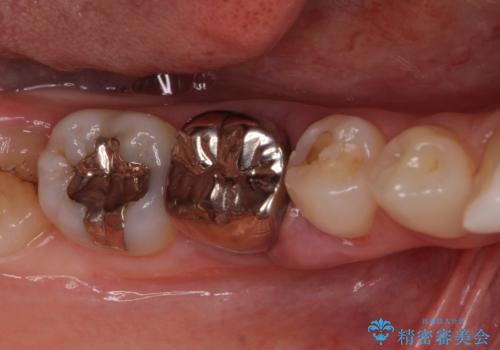

[入れ歯にしたくない] 臼歯部インプラント補綴